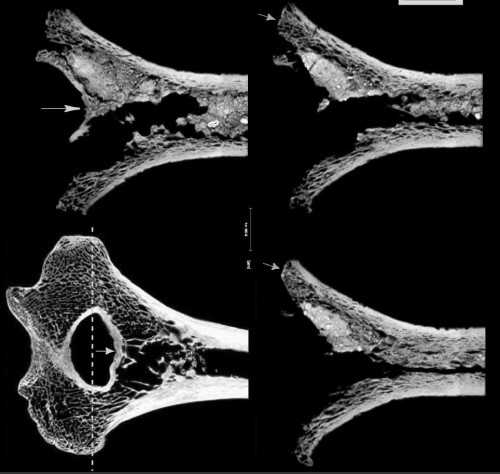

Сверху — сросшаяся ключица, снизу — локтевая кость Крапина 180, со следами предположительной ампутации нижнего конца. Источник:

Вернёмся в Крапину. Крапина 180 — правая локтевая кость, нижняя треть которой отсутствует. О том, что часть кости «потерялась» при жизни, говорит образовавшаяся костная мозоль — свидетельство длительных процессов регенерации костной ткани. Такое бывает именно при ампутации… Впрочем, другая возможная причина — врождённое отсутствие части руки у бедного калеки. А ещё бывает такая штука — ложный сустав (или псевдоартроз), это осложнение при переломе, когда кость не срастается, а на месте перелома формируется что-то вроде дополнительного сустава, с настоящими суставными поверхностями и т. п. Псевдоартроз может давать картину, похожую на ту, что мы видим в случае Крапины 180. Увы, строго доказать ни одну версию невозможно.

Ещё один неандертальский кандидат на ампутацию — наш старый иракский знакомый, старичок Шанидар 1. Среди длинного списка травм и патологий этого замечательного скелета — потерянная внешняя часть правой плечевой кости. Кость, вообще-то, была сломана в двух местах, и внешний её конец — уплощённый, с обширным обнажением трабекулярной ткани, а также общая атрофия кости — наводят на мысль об ампутации, либо о несросшемся переломе (опять ложный сустав?)… Известный антрополог Эрик Тринкаус высказывает предположение, что рука, действительно, могла быть ампутирована чуть выше локтя, хотя не исключает версию псевдоартоза (просто часть кости могла потеряться уже после смерти неандертальца). По крайней мере, человек прожил после травмы длительное время.

Правая лопатка и плечевая кость Шанидар 1. Источник: Trinkaus, 1982, p. 63.